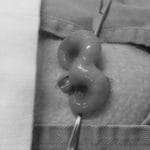

当院はウサギ・小動物・爬虫類・鳥類などのエキゾチックアニマル専門の病院です。

エキゾチックアニマルの診療

専門的なエキゾチックアニマル診療を提供しています。爬虫類、鳥類、小動物など、幅広い種類に対応。専門知識と経験を活かしたケアを提供。